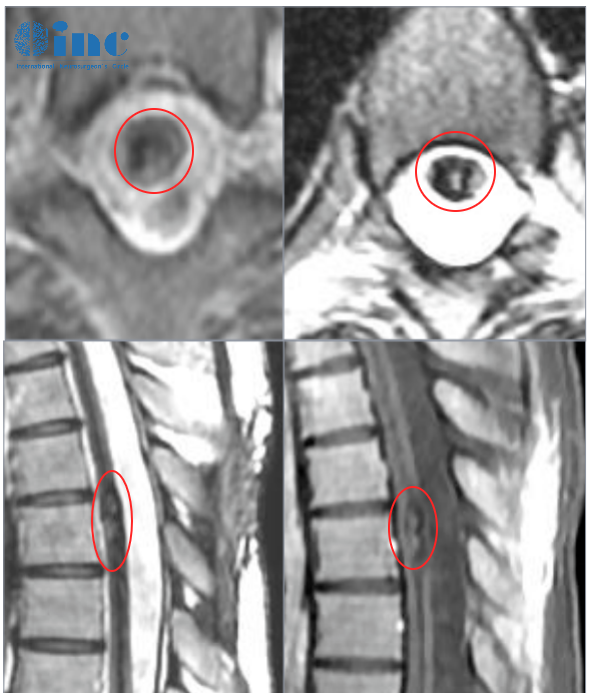

双侧丘脑海绵状血管瘤导致Monro双孔脑脊液阻塞

20岁的田田是一名在校大学生,在一次参加完常规体育运动后自感后背轻微疼痛,两天后出现双下肢无力,检查诊断胸髓髓内出血性病变。后续病情进展很快,还出现小便困难,双下肢无力加重等症状。再次检查后确诊胸髓髓内6海绵状血管瘤,医生考虑血管瘤位置比较深,在腹侧,手术风险大,建议保守治疗。去年,田田出现右下肢麻木感,检查考虑二次出血。两天内症状急剧加重,双下肢运动功能丧失,大小便失禁。为了缓解田田的症状,医院随即进行下胸后路椎管扩大减压术,但是并未对血管瘤进行切除。看到女儿一次又一次病情加重而又无能为力,得知巴教授来华的消息后,他们重新看到了希望……

“这次手术的目的是把现在存在的血管瘤拿掉,因为这个海绵状血管瘤还会再次出血,造成症状会更严重,整个肢体活动可能完全就没有了。我们现在是把这个血管瘤拿掉了之后,通过康复运动,使肌力再次增加,缓解现在的症状。主要目的还是把血管瘤拿掉,防止再出血造成更大的损害。而且从影像上看,脊髓损伤的还不是很严重,孩子还年轻,症状能够减轻机会还是大的。手术之后就可以开始轻缓的康复练习,两三周之后就可以开始康复运动……”